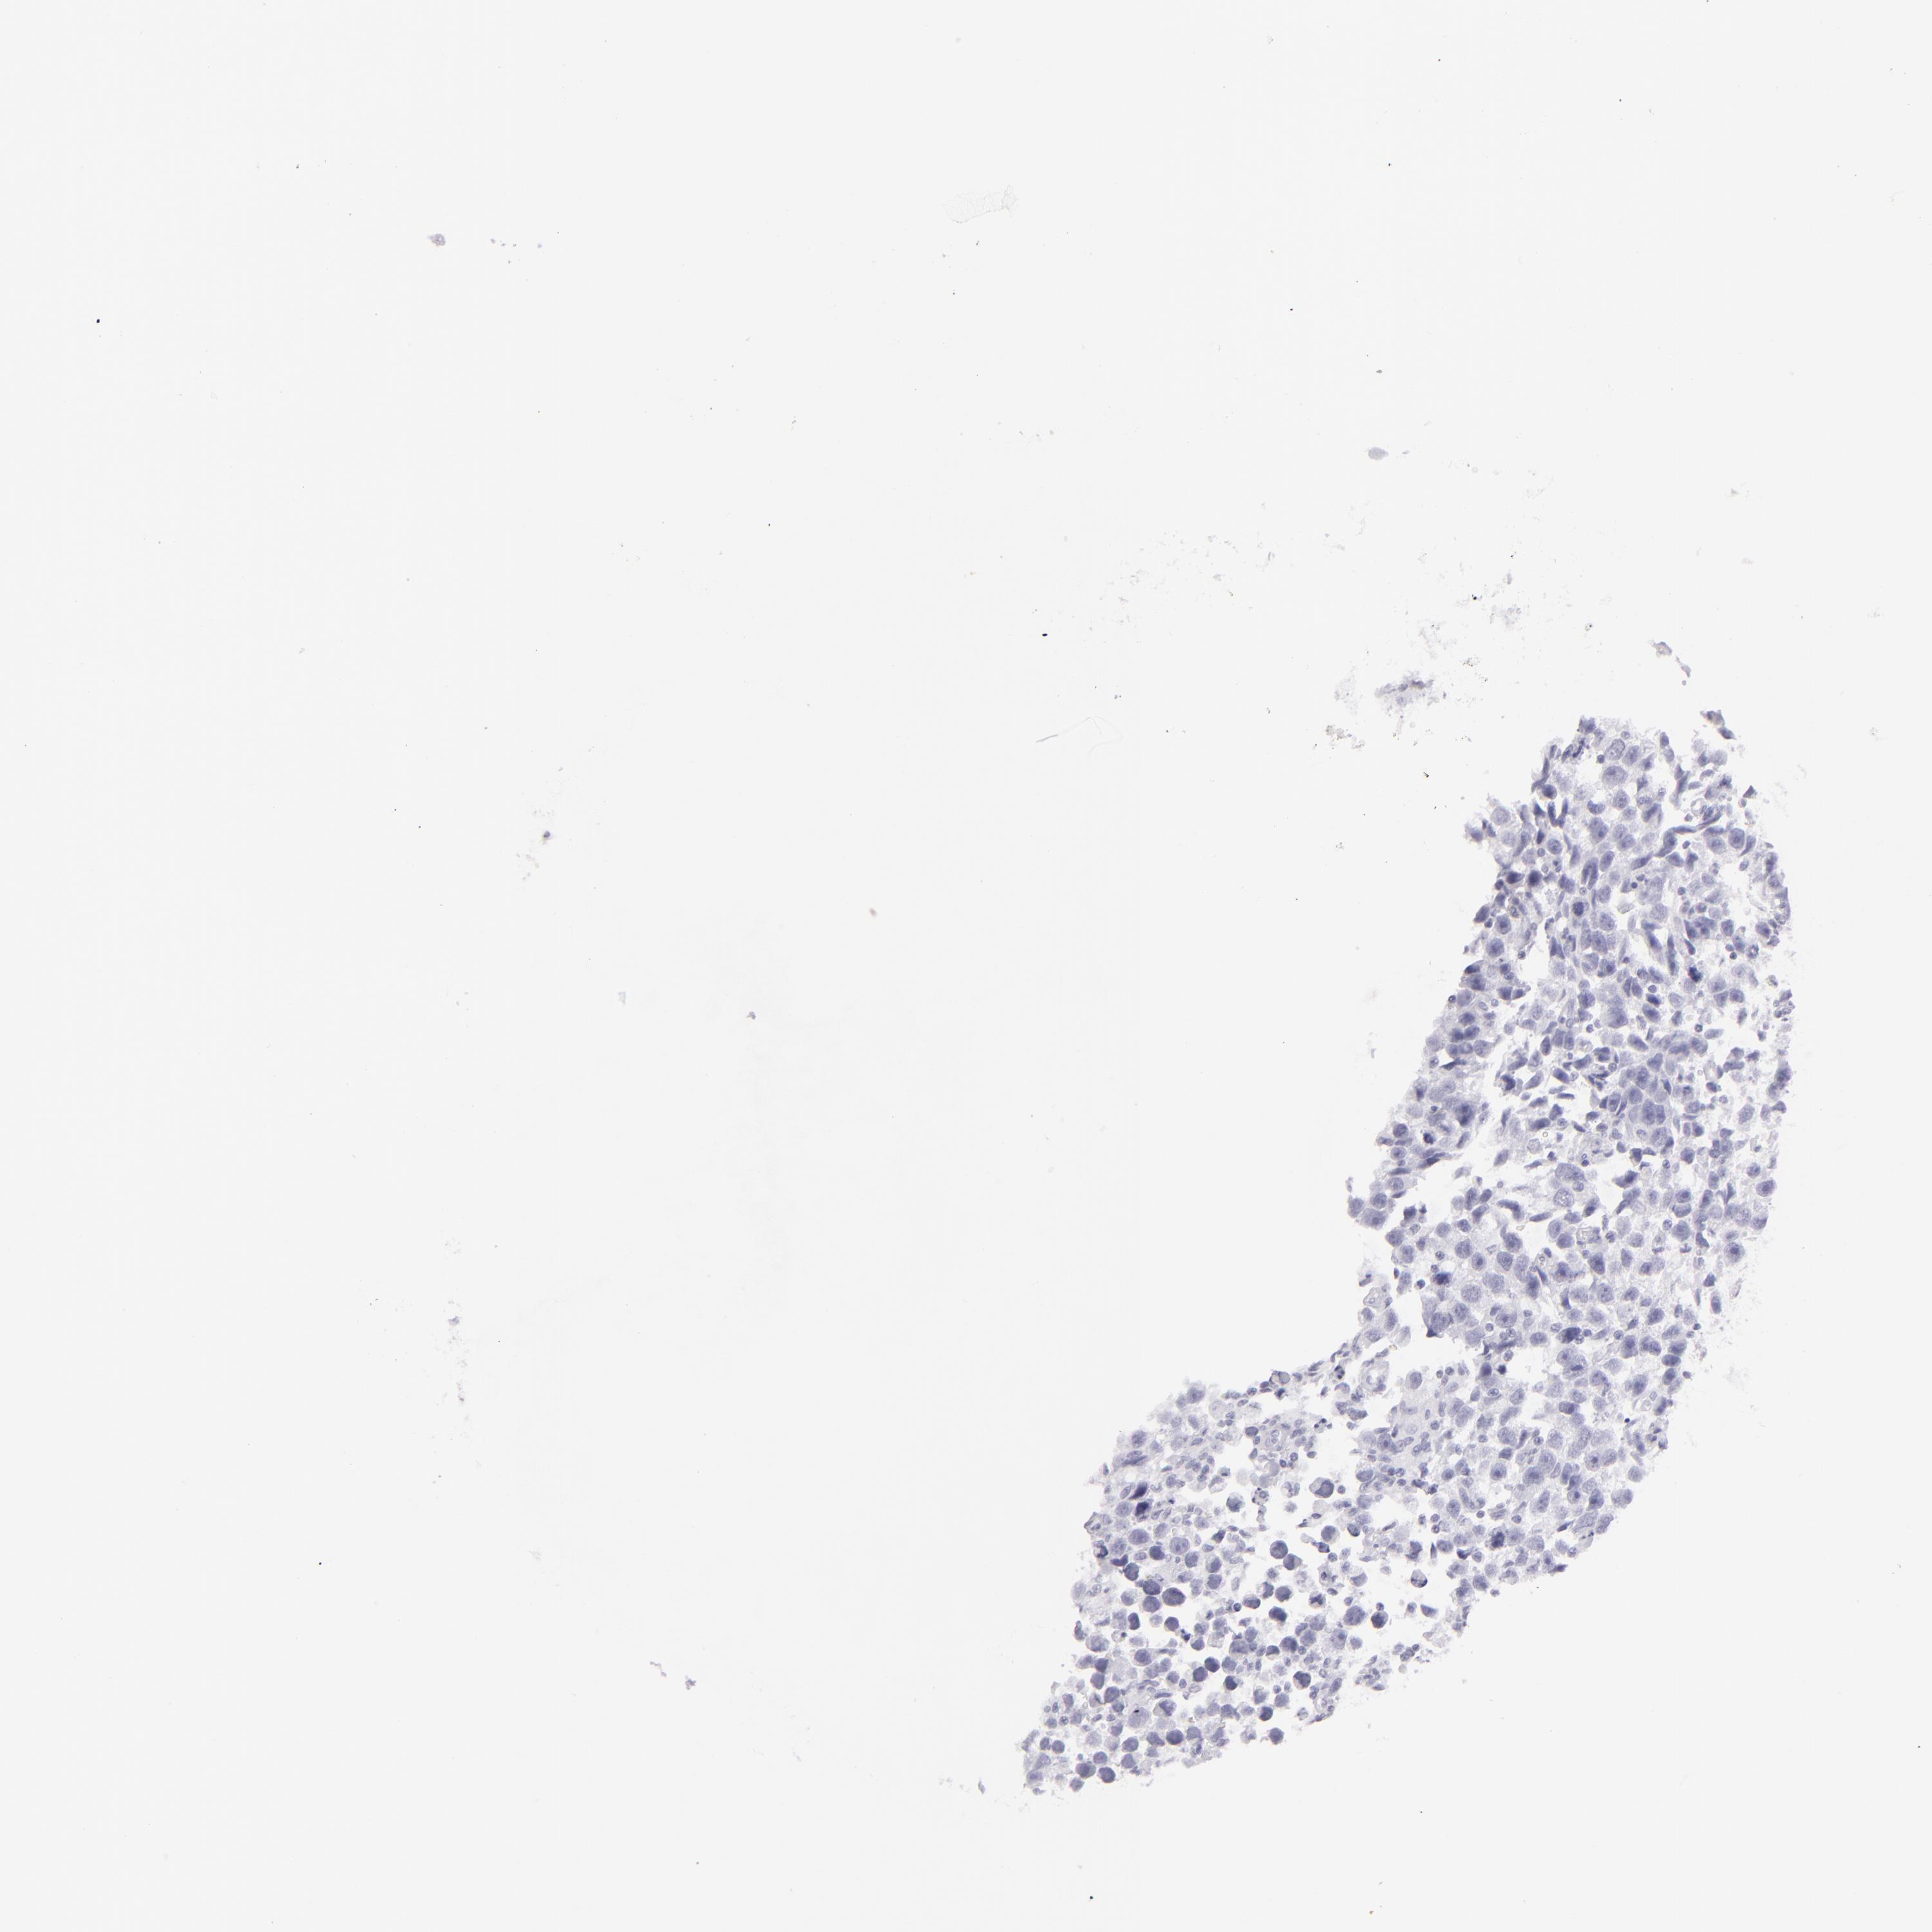

TESTIS CANCER - Protein expressioni

A mouse-over function shows sample information and annotation data. Click on an image to view it in a full screen mode. Samples can be filtered based on level of antibody staining by selecting one or several of the following categories: high, medium, low and not detected. The assay and annotation is described here.

Note that samples used for immunohistochemistry by the Human Protein Atlas do not correspond to samples in the TCGA dataset.

Antibody stainingi

Antibody staining in the annotated cell types in the current human tissue is reported as not detected, low, medium, or high, based on conventional immunohistochemistry profiling in selected tissues. This score is based on the combination of the staining intensity and fraction of stained cells.

Each image is clickable and will lead to virtual microscopy that enables deeper exploration of all samples and also displays staining intensity scores, fraction scores and subcellular localization as well as patient and tissue information for each sample.

Antibody HPA030188

Antibody HPA030189

Antibody CAB002210

Carcinoma, Embryonal, NOS

Seminoma, NOS